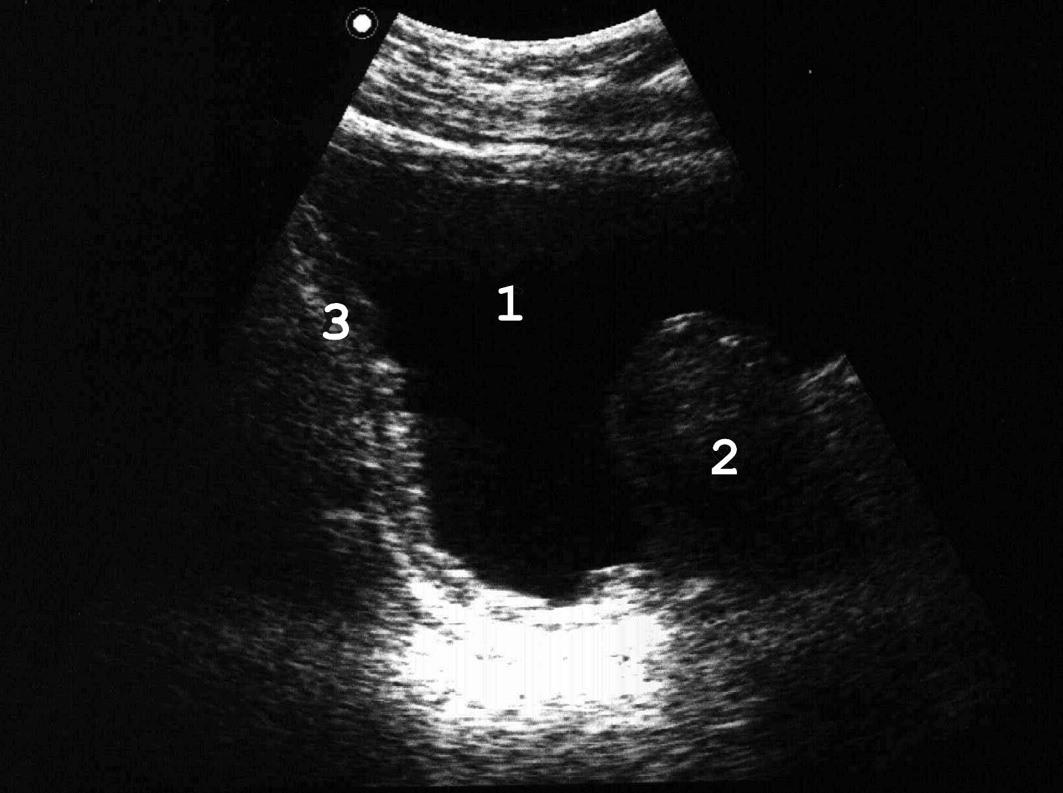

Рис. 2. Сонограмма мочевого пузыря женщины в норме. Ориентиры треугольника Льето: 1 − устья мочеточников; 2 − внутреннее отверстие мочеиспускательного канала. (Попе-речное и продольное сканирование, конвексный датчик 5 МГц, “Logiq-500”).

При осмотре области мочепузырного треугольника в большинстве случаев можно увидеть устья мочеточников (рис. 2), оценить симметричность их расположения, измерить расстояние между ними.